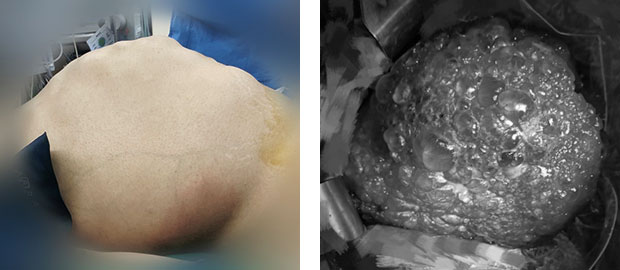

患者术前腹部 巨大多囊肝

41岁的李女士患多囊肝已有14年之久,期间辗转各地治疗,饱受病痛折磨。当李女士来到我院时,整个人已瘦骨嶙峋,巨大膨隆的肚子宛若怀胎十月,与体型极不相称,密集的囊包在肚子上清晰可见。由于巨大的多囊肝几乎占据了她腹部的全部空间,胸腹腔内脏器官受压,导致进食困难、腹压升高,腹腔脏器均出现不同程度的移位,日常活动受到严重影响,上下楼梯都变得非常困难。

影像学可见巨大多囊肝占据腹腔

患者术后恢复正常体型

术后,在医护人员的精心照料下,患者渡过了危险期,目前已恢复正常生活。“感觉轻松了许多,整个人如获新生。”李女士看着自己平坦的肚子如是说。